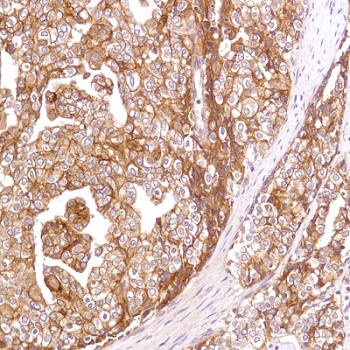

CD 47 is an integrin-associated protein, a member of the immunoglobulin superfamily, with a molecular weight of 50 kDa. It is widely expressed in normal tissues, including erythrocytes. SIRPα on the surface of macrophages can bind to CD47 and exert immunosuppressive effects. When tumor cells highly express CD47, it can also bind to SIRPα on the surface of macrophages, thus protecting tumor cells from phagocytosis and clearance by macrophages, which is one of the mechanisms of immune escape of tumor cells.

CD47 Antibody Reagent binds specifically to CD47 molecular antigen. Immunohistochemistry kits containing CD47 Antibody Reagent are suitable for the evaluation of therapeutic targets for leukemias, lymphomas, and solid tumors.